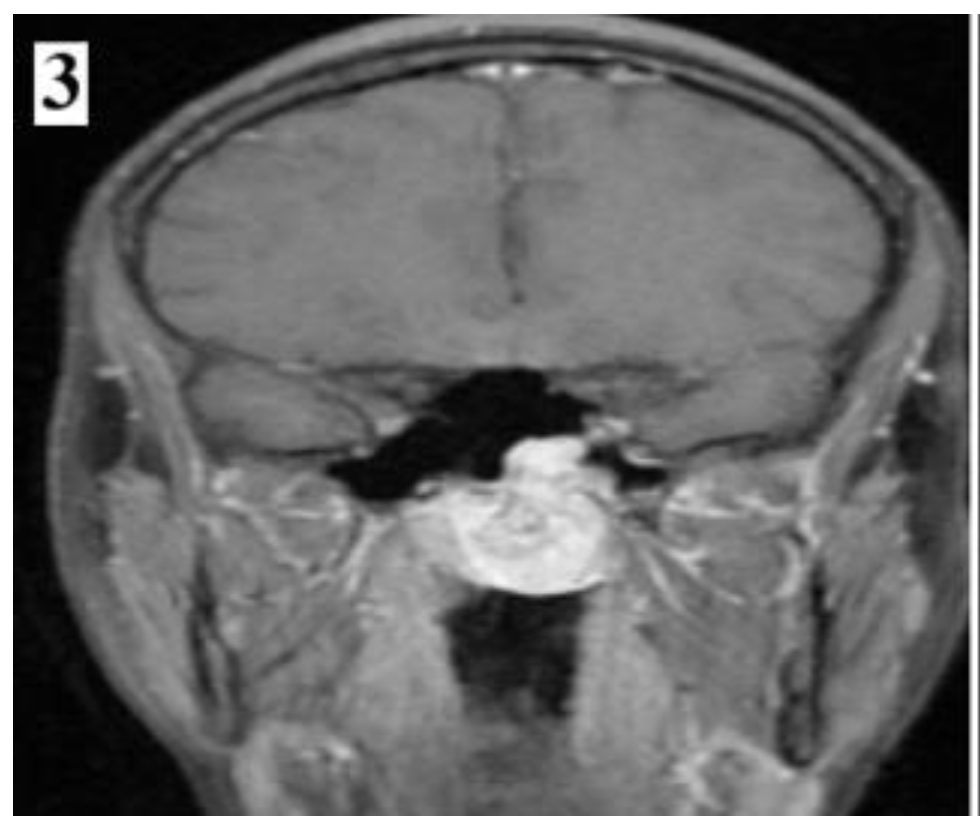

Figure 8.

Preoperative MRI of a stage IIC juvenile angiofibroma. The Holman-Miller sign (the anterior bowing of the posterior maxillary wall) on the CT scan (part 2).